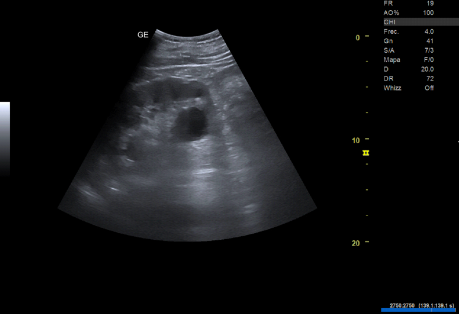

- Ecografía clínica renovesical: Vejiga sin lesiones ocupantes de espacio, sin residuo postmiccional, próstata de tamaño aumentado (56 cc). Ambos riñones con quistes corticales simples, de hasta 9,6 cm en el riñón izquierdo. Sistema excretor derecho no dilatado. Leve-moderada dilatación pielocalicial izquierda. No se evidencian imágenes ecográficas sugestivas de litiasis en pelvis renal.

- Resonancia magnética renal con contraste: hidronefrosis grado II izquierda, secundaria a litiasis obstructiva de 5 mm localizada en el tercio inferior del uréter, inmediatamente caudal al cruce con los vasos ilíacos. Quistes sinusales y simples corticales bilaterales, el mayor de 9,4 cm de eje craneocaudal en el polo inferior del riñón izquierdo. Resto sin alteraciones significativas.